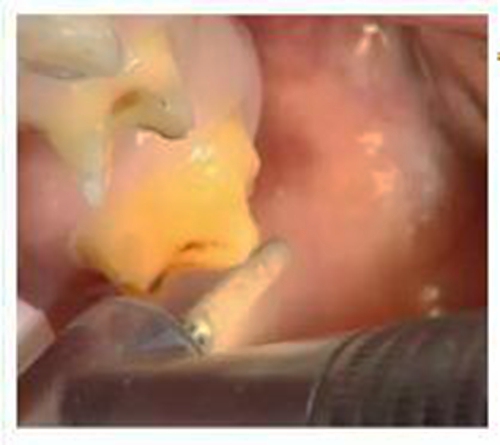

牙體預(yù)備是牙科修復(fù)中非常重要的一個(gè)步驟,如何讓預(yù)備更準(zhǔn)確,效果更好,就需要牙醫(yī)在操作的過(guò)程中掌握操作細(xì)節(jié)。

一、預(yù)備牙體

備牙后需要使用沙粒較細(xì)的車針過(guò)順,使表面平溜,更易于修復(fù)體就位。

備牙注意: